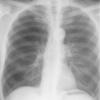

severe copd

Date: 06/06/2004

Views: 7591